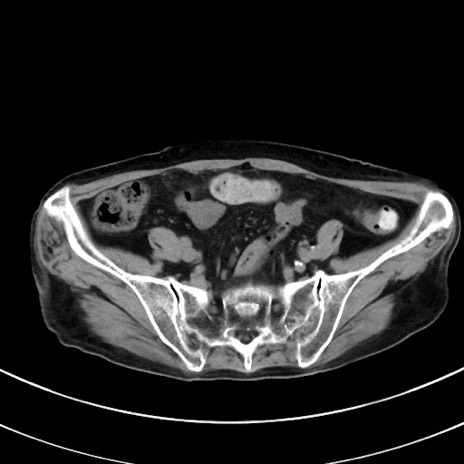

症例33(横断像)

【症例】70歳代 女性

【主訴】心窩部痛

【現病歴】延髄病変の精査・加療にて神経内科入院中。本日より心窩部痛あり。

【既往歴】虫垂炎

【身体所見】右下腹部を中心に圧痛と反跳痛あり。

【データ】WBC 10900、CRP 0.02